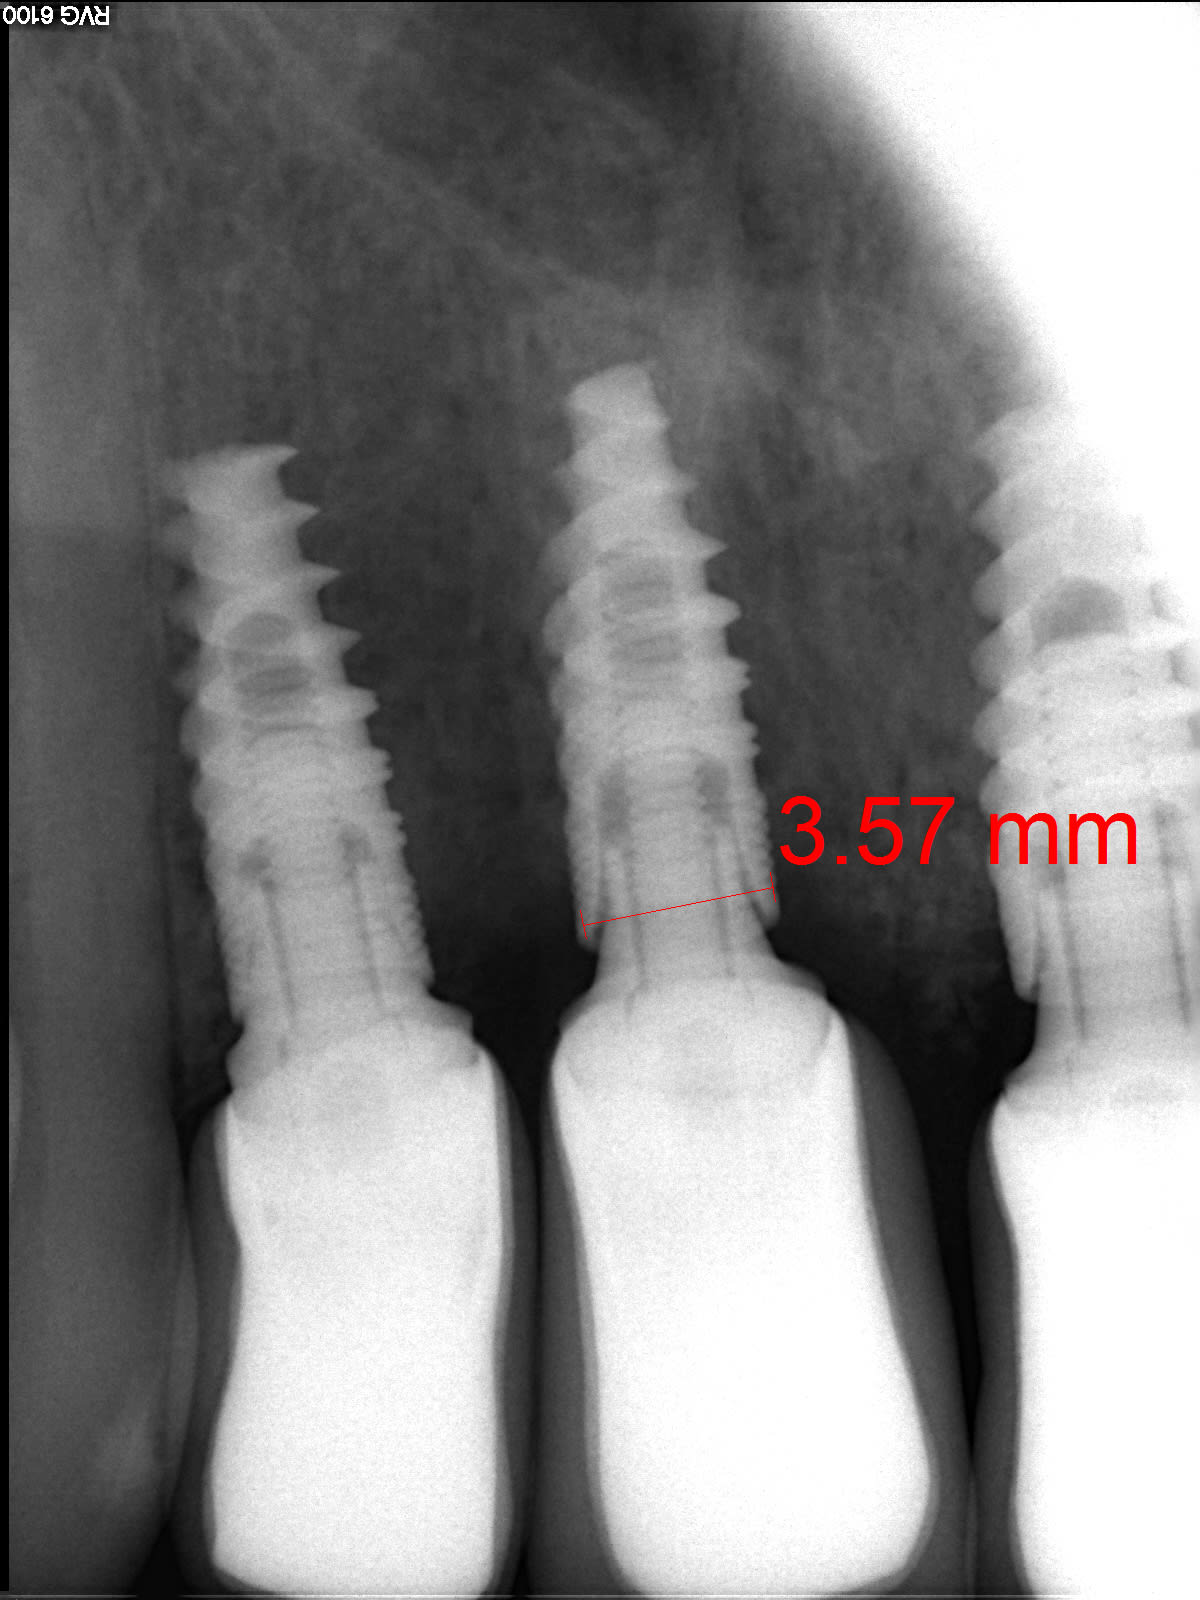

Un dentiste des USA m'a contacté pour savoir si ces implants sont de marque française. L'implant le plus distal est un Nobel Activ je pense mais les deux autres ne semblent pas être de Nobel puisqu'il y a des microfilets et non des rainures.

Vos avis s'il vous plait?

bein non c'est bien des Nobel active...

tu as l'impression que c'est des minispires à cause de l'angulation de la radio...;-)